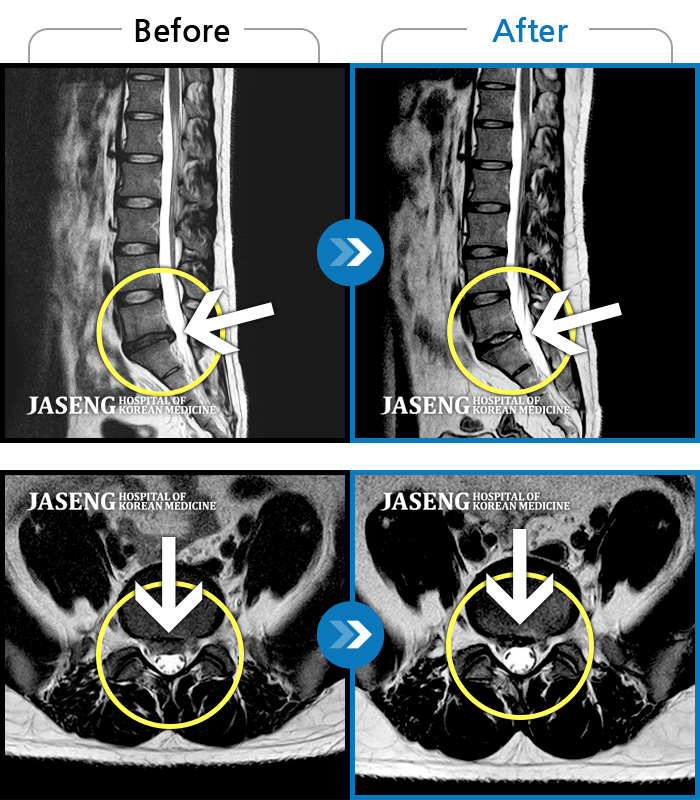

허리디스크

천안 · 윤영웅 원장

허리, 둔부 및 다리로 통증과 저림이 심해서 옆으로 잘 수 없어요.

촬영시기

2021.04.05 ~ 2022.03.25

2022.03.25

조회수 174